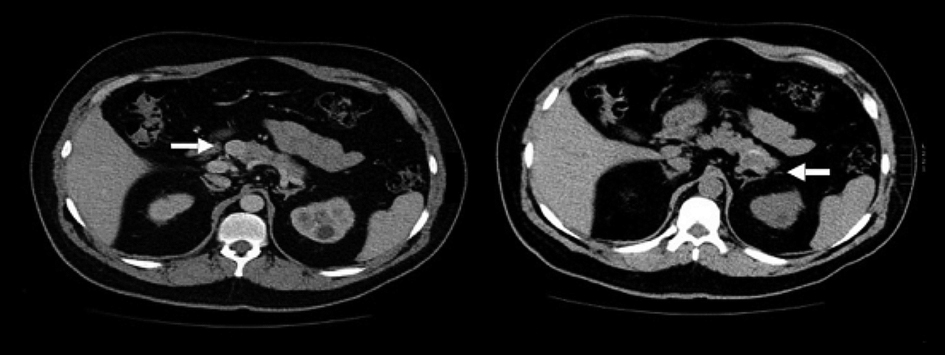

Hombre de 36 años con antecedente de resección de meningioma parietal en 2010 y cistolitotripsia por litiasis renal bilateral en 2013. En 2010, después de la resección del meningioma, empezó a padecer crisis convulsivas parciales complejas (cuatro eventos semanales) durante cuatro años, atribuidas al evento neuroquirúrgico; sin embargo, todos los eventos fueron asociados a hipoglicemia capilar de hasta 38 mg/dL. Fue referido a un hospital de tercer nivel del Instituto Mexicano del Seguro Social (IMSS) y fue atendido en el Servicio de Endocrinología, donde se cuantificaron los niveles de glucosa sérica en ayuno, 27 mg/dL, y no presentó síntomas neuroglucopénicos. Se realizaron determinaciones de insulina (37.3 mcmUI/mL), péptido C y proinsulina que resultaron elevadas y se documentó la presencia de hipercalcemia (≥ 12 mg/dL), hipofosfatemia persistente y elevación de paratohormona (PTH 421.9 pg). Se efectuó ultrasonido endoscópico, que mostró lesión hipoecogénica en la cola del páncreas de 2.3 x 1.3 cm. La tomografía toracoabdominal evidenció una lesión en la cabeza de páncreas de 10 mm, hipodensa y homogénea con el medio de contraste y otra lesión en cola de 18 mm sin reforzamiento (figura 1); asimismo, presentó litiasis renal bilateral con dilatación ureterovesical izquierda. También se estudió al paciente con un gammagrama, el cual presentó tejido paratiroideo hipercaptante en porción inferior y posterior del lóbulo tiroideo izquierdo (figura 2), asociado a elevación de los valores de la hormona paratiroidea (PTH), lo que corroboró la presencia de hiperparatiroidismo primario. La resonancia magnética no mostró evidencia de adenoma hipofisario. Ante la hipoglicemia persistente a pesar del tratamiento, se decidió la resección quirúrgica de las lesiones pancreáticas. Durante la evolución postquirúrgica se normalizaron las cifras de glucosa (107 mg/dL) e insulina.